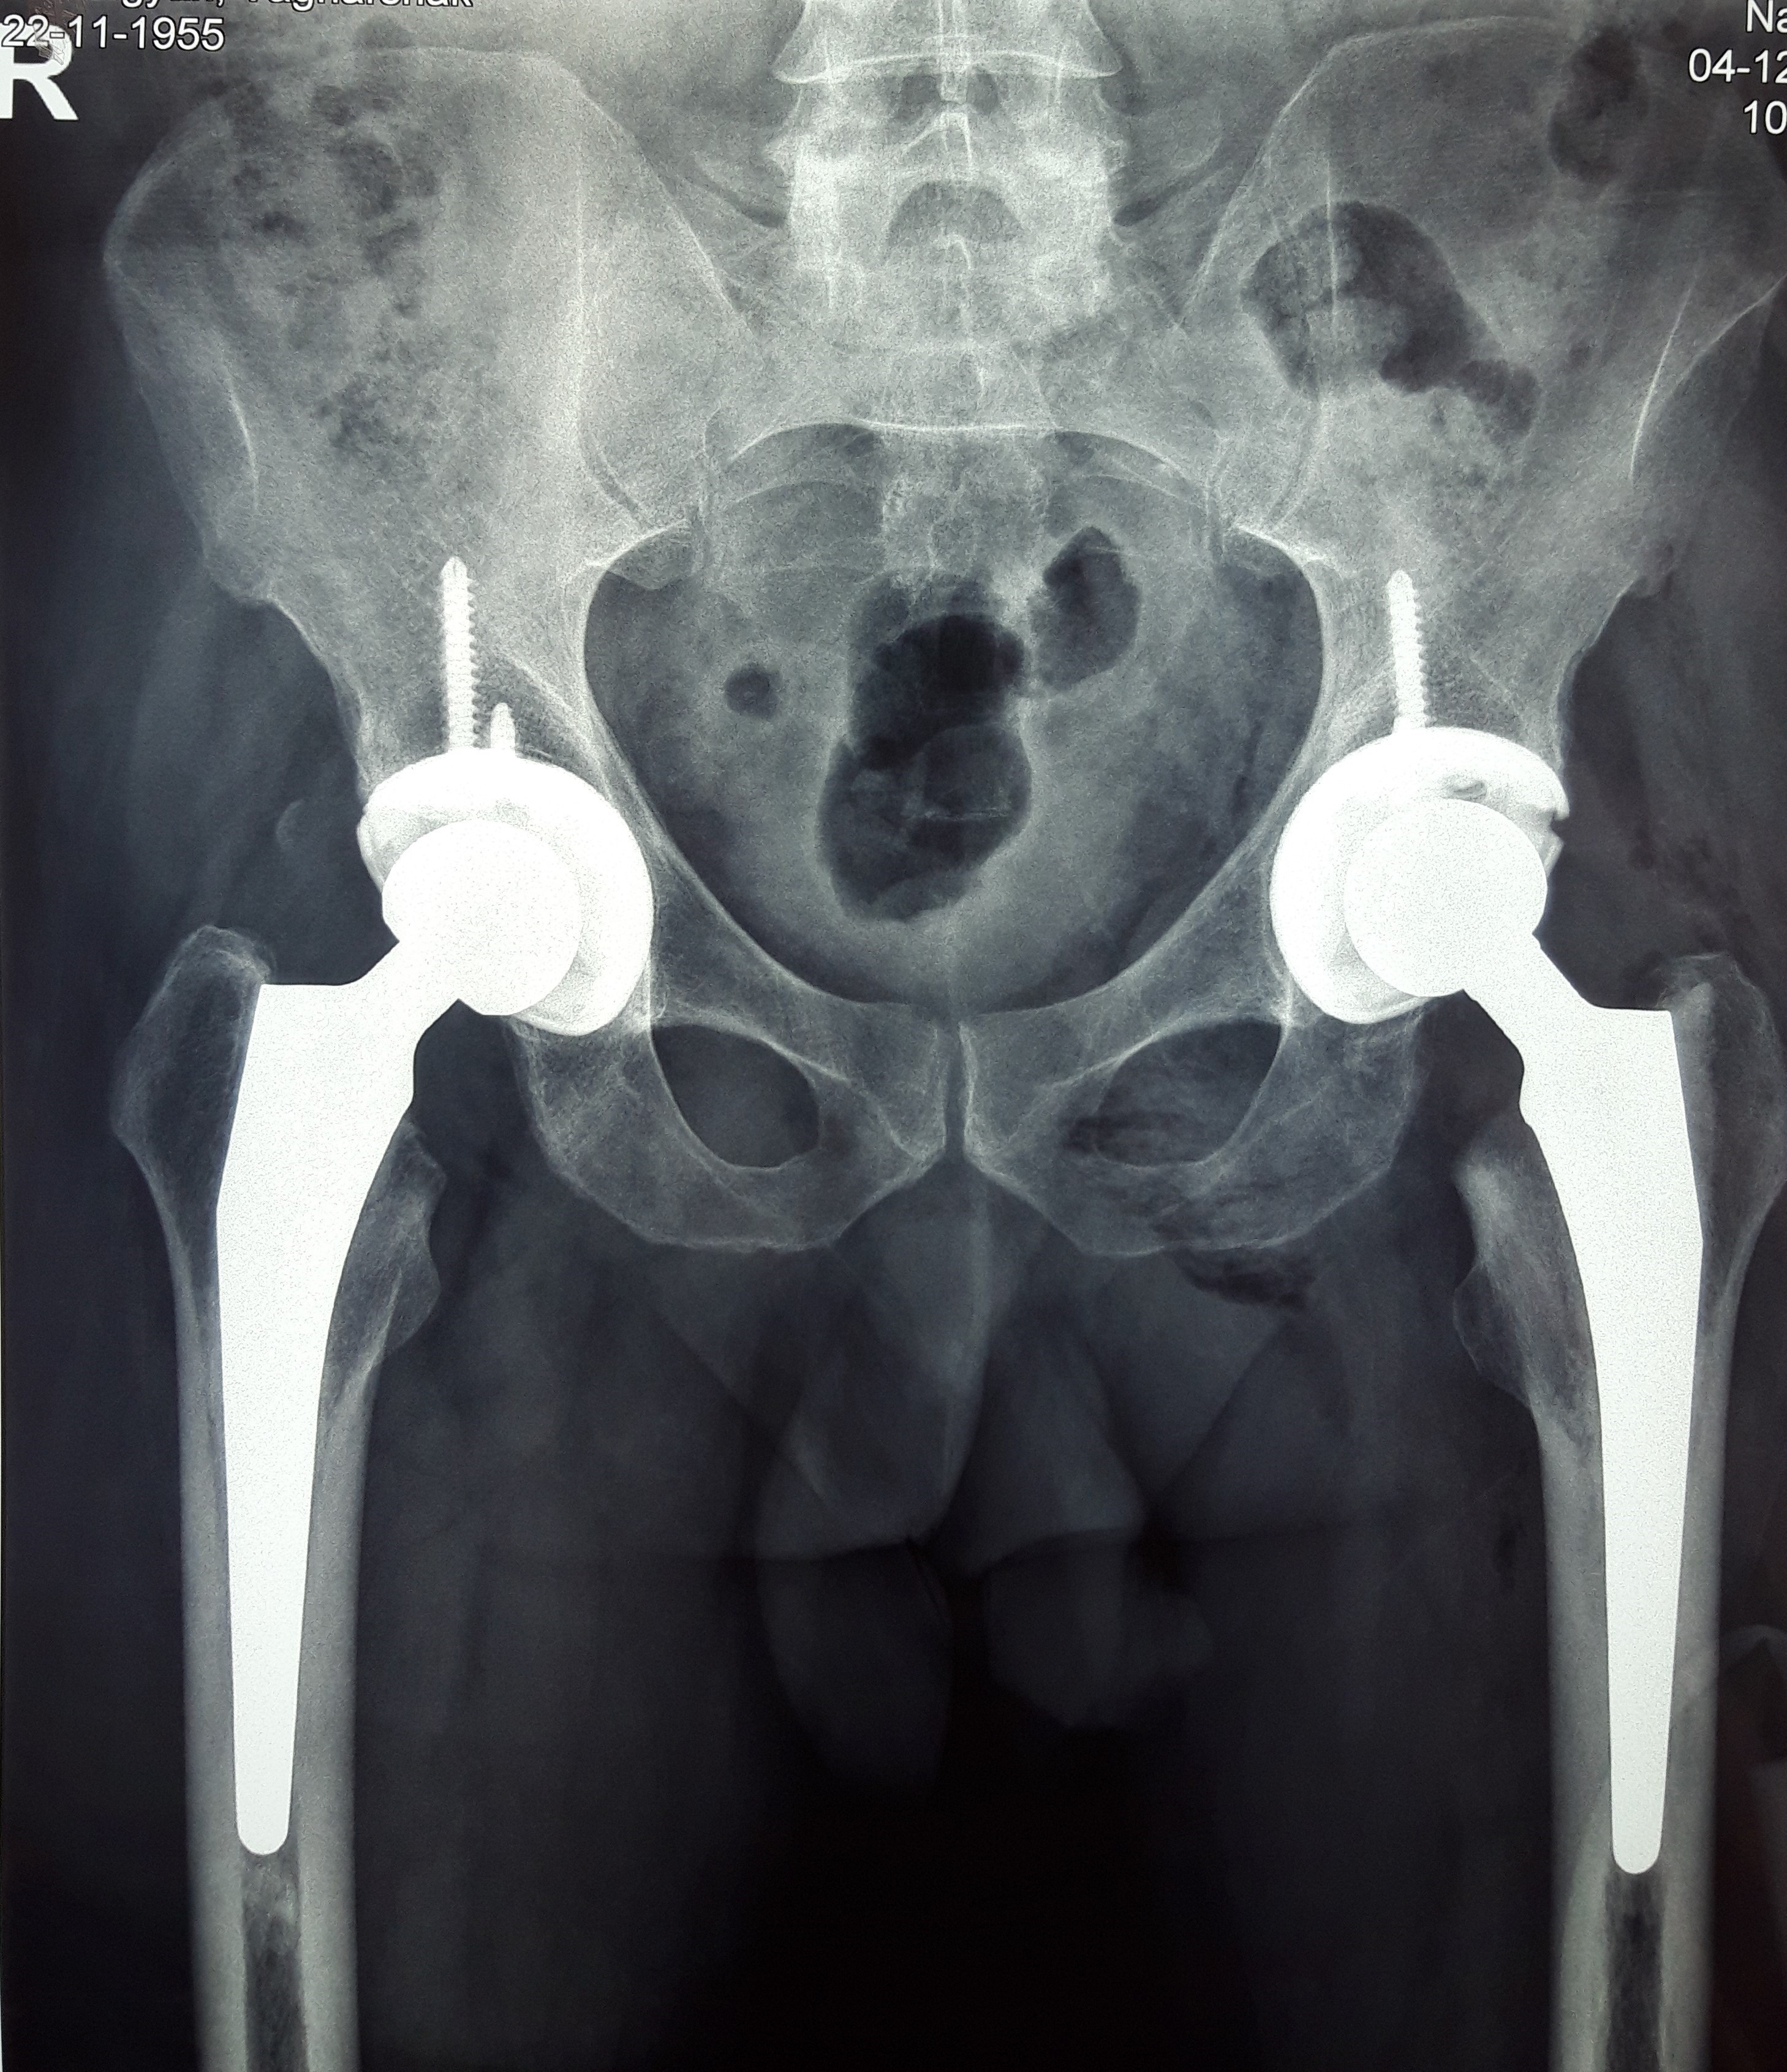

նկար 3․ Նախքան վիրահատությունը նկար 4․ Վիրահատությունից 5 տարի անց